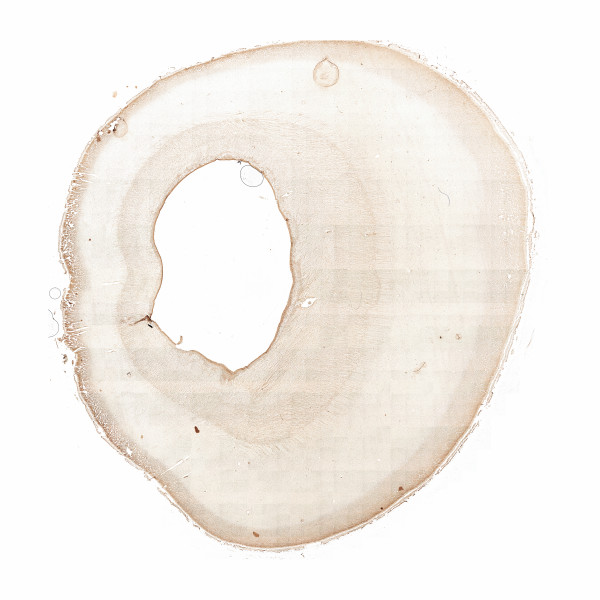

Human brain 22th gestational week

IHC 22th gw

Ki67

Ki67 N1_1550 20%